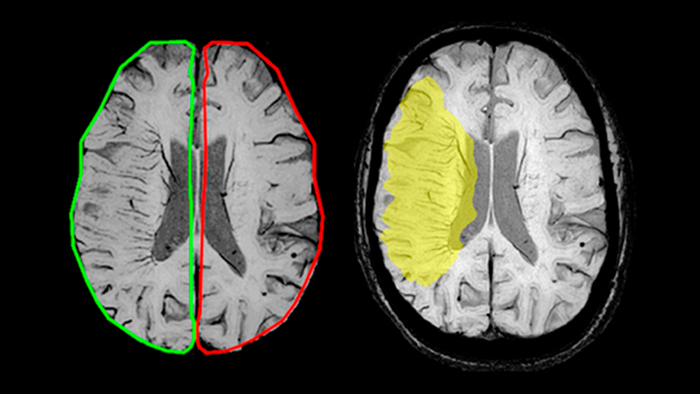

Магнитно-резонансная томография (МРТ) играет важную роль в диагностике неврологических заболеваний. Классические последовательности, применяемые в клинической практике, отражают такие ключевые параметры тканей, как: времена релаксации T1, T2 и T2*, измеряемый коэффициент диффузии и протонную плотность. Широко применяются последовательности, взвешенные по T1 и T2, инверсия-восстановление с подавлением воды (FLAIR) и диффузионная МРТ (рис. 1).

SWIp активно используется для визуализации точечных кровоизлияний в глубоком подкорковом белом веществе, которые сопровождают диффузные аксональные повреждения головного мозга. Клинический прогноз зависит от числа кровоизлияний, а недавнее исследование [11] выявило связь между кровоизлияниями в ряде глубоких подкорковых областей головного мозга и повышенной вероятностью нарушения исполнительных функций у подростков. Таким образом, остро стоит необходимость обнаружения и точной локализации церебральных микрокровоизлияний [12]. Эти точечные патологические изменения при диффузно-аксональном повреждении не столь заметны при использовании традиционных методик МРТ-визуализации (рис.8). Использование фазовой информации обуславливает более высокий контраст кровоизлияний на SWI изображениях, как следствие, даже чувствительные к неоднородностям поля T2* последовательности уступают SWI изображениям по чувствительности при диагностике диффузных аксональных повреждений [13].